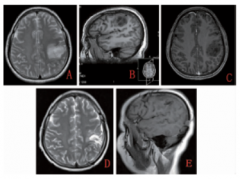

脑胶质细胞瘤偏良性者生长缓慢,病程较长,自出现症状至就诊时间平均两年,而恶性者瘤体生长快,病程短,自出现症状到就诊时多数在三个月之内,70%-80%多在半年之内。另外,恶性胶质瘤在PETCT,CT等影像学检查中的显现也是有所不同的。以PETCT为例,一般一、二级星形细胞瘤大多表现为颅内低密度灶,类似水肿。三四级星形细胞瘤病灶密度则是不均匀,肿瘤内的高密度常为出血或钙化,低密度为肿瘤的坏死或囊变区。

良恶性肿瘤的简单的判断方法,包括以下几种: 1、临床症状区分,一般良性脑部肿瘤的临床症状较轻,时间跨度较长,一般在3个月或6个月以上,可以是简单头痛持续3-6个月。恶性肿瘤发病时间、病程较短,症状较重,如头痛是剧烈的头痛,比良性肿瘤头痛更急、更快,表现更重,一般症状持续一周到一个月才会就医。恶性肿瘤头痛发作频率比良性肿瘤多; 2、影像学辨别,良性脑肿瘤都有完整包膜,影像学如脑膜瘤、神经鞘瘤都生长在大脑外表面,肿瘤周边存在完整包膜。恶性脑肿瘤包括胶质瘤,它出现在颅脑内部,边界不清,呈弥散性分布,所以通过影像学检查可以简单进行区分,进行相应增强扫描可以更加明确肿瘤边界,明确肿瘤性质。